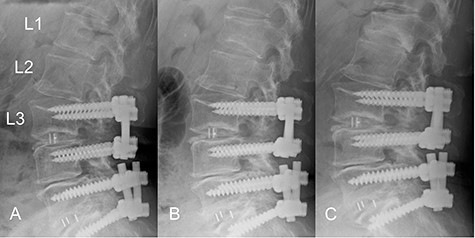

The patient was an 82-year-old Japanese woman who had presented 2 months earlier with pain and numbness in her left lower extremity. She had a history of vertebral fracture at L1 4 months previously for which she had been treated with a lumbar orthosis for 2 months (Fig. 1). Magnetic resonance imaging of the lumbar spine demonstrated foraminal stenosis at the L2–L3 level (Fig. 2A). CT images of the lumbar spine revealed ossification in the capsular portion of the ligamentum flavum around the L2–L3 facet joint (Fig. 2B–D). She underwent L2–L3 foraminotomy with excision of the capsular portion of the OLF. The patient’s symptoms disappeared immediately after surgery. Postoperative CT scans showed good decompression at the operated level (Fig. 2E and F).

Magnetic resonance and computed tomography (CT) images acquired at the time of onset of radiculopathy. (A) Sagittal T1-weighted magnetic resonance image showing moderate foraminal stenosis at the L2–L3 level. (B) Sagittal CT image showing ossification of the ligamentum flavum protruding into the foramen. (C, D) Axial CT image showing OLF in the capsular portion. (E, F) Postoperative CT image confirming adequate removal of the ossification of the ligamentum flavum.